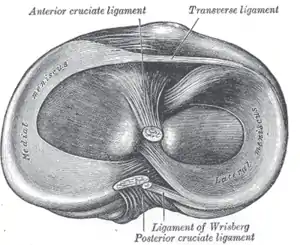

Its anterior end is attached in front of the intercondyloid eminence of the tibia, lateral to, and behind, the anterior cruciate ligament, with which it blends; the posterior end is attached behind the intercondyloid eminence of the tibia and in front of the posterior end of the medial meniscus.

The anterior attachment of the lateral meniscus is twisted on itself so that its free margin looks backward and upward, its anterior end resting on a sloping shelf of bone on the front of the lateral process of the intercondyloid eminence.

Close to its posterior attachment it sends off a strong fasciculus, the ligament of Wrisberg, which passes upward and medialward, to be inserted into the medial condyle of the femur, immediately behind the attachment of the posterior cruciate ligament.

The lateral meniscus gives off from its anterior convex margin a fasciculus which forms the transverse ligament.

Left knee joint from behind, showing interior ligaments.

Left knee joint from behind, showing interior ligaments. Right knee-joint, from the front, showing interior ligaments.